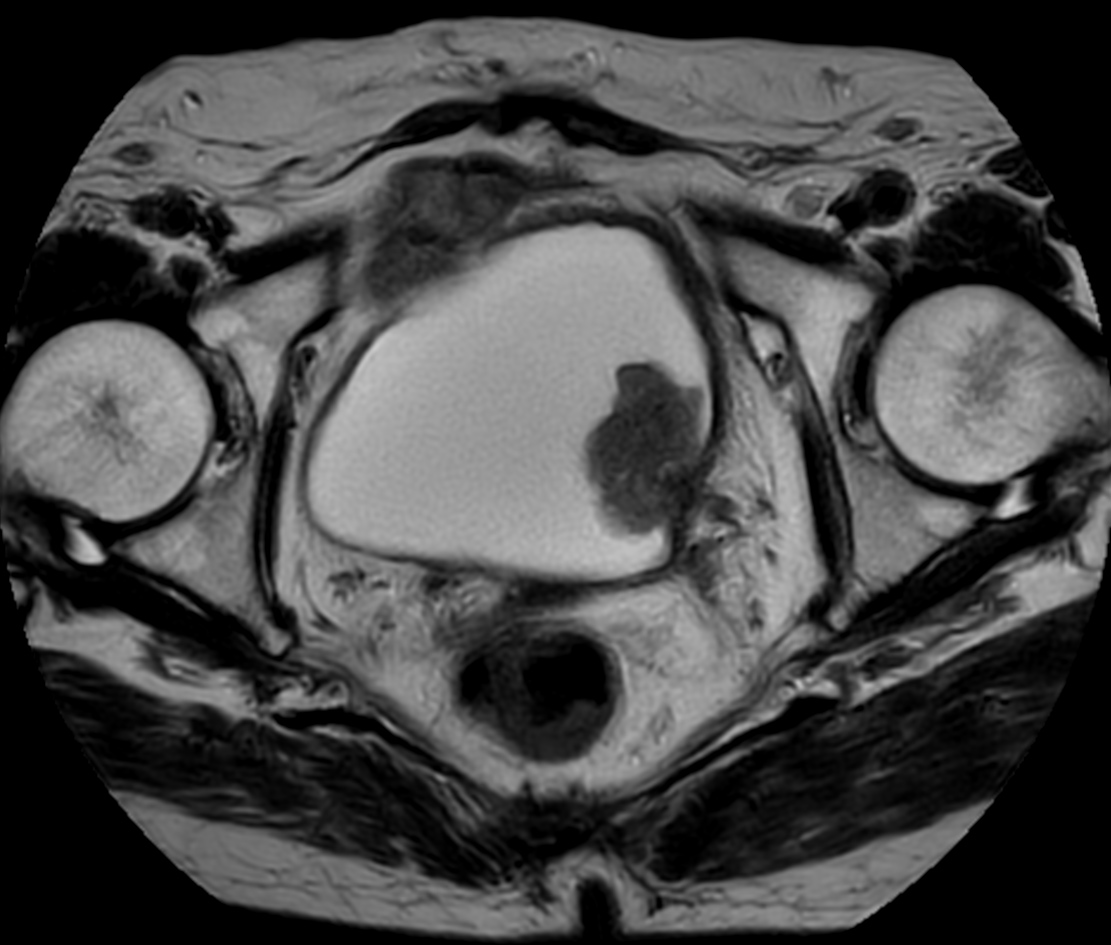

Patient with bladder cancer. The ExamCard includes techniques for motion reduced imaging (MultiVane XD), 3D TSE imaging (PelvisVIEW) allowing for multiple image directions in one single scan, a multi-phase contrast-enhanced sequence (4D FreeBreathing) to improve imaging confidence and Compressed SENSE to accelerate the entire exam.

T1w TSE MultiVane XD